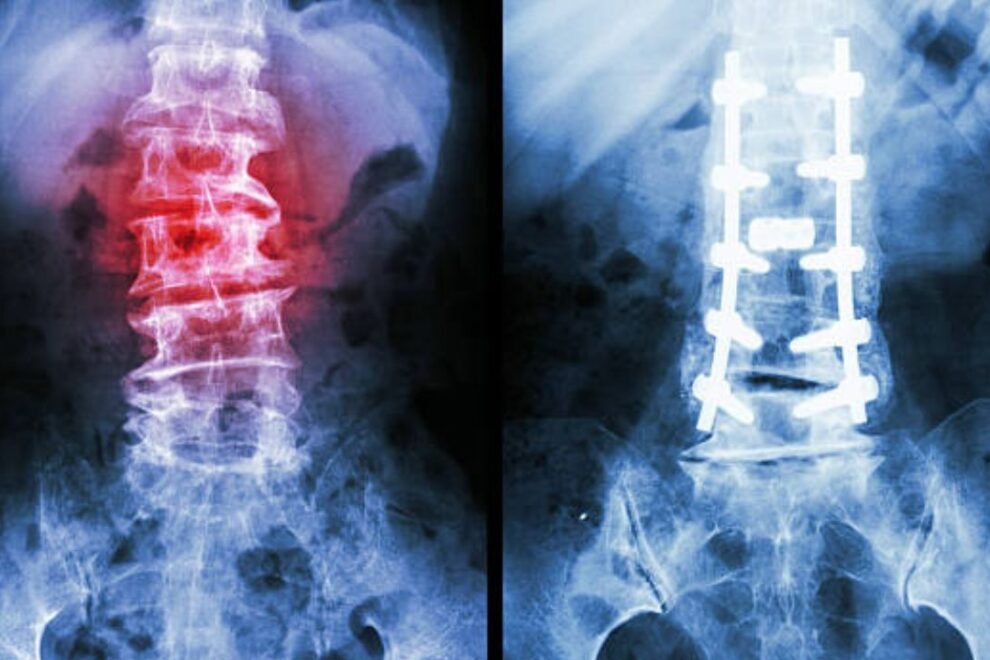

X-rays may be necessary in order to measure the curvature. Depending on the degree of the curvature and whether it gets worse over time, the doctor may recommend treatment.

Adolescent Idiopathic Scoliosis is the most common form of scoliosis. If the curve is small when first diagnosed, it can be observed and followed with routine X-rays and measurements. If the curve stays below 25 degrees, no other treatment is needed. If the curve is between 25-40 degrees, a brace may be recommended. If the curve is greater than 40 degrees, then surgery may be recommended.

People with degenerative scoliosis will often have more complaints of back and leg pain. This is related to the arthritis in the back and possible compression of the nerve roots that lead to the legs. Nonoperative treatment including physical therapy, exercises, and gentle chiropractic can help relieve these symptoms in some cases. People who fail to improve with these treatments may benefit from surgery. X-rays and possible MRIs will be obtained to plan for surgery. The surgery could include only a decompression or removal of bone spurs that are compressing the nerves. In some cases, a fusion will be necessary to stabilize the spine and possibly correct the abnormal curve.